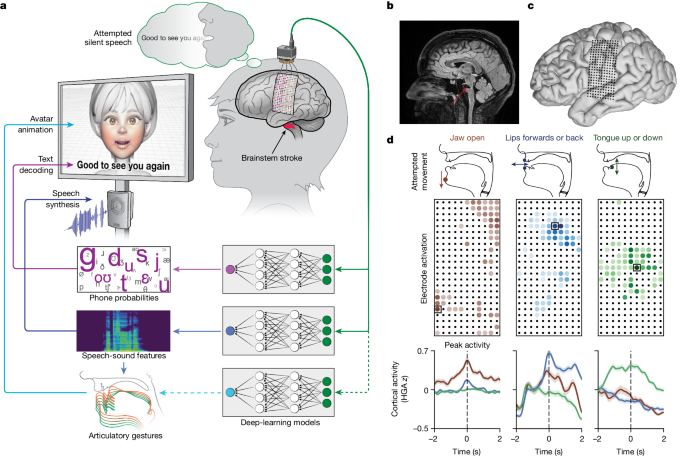

این دستگاه با استفاده از الکترودهای حساس و الگوریتمهای هوش مصنوعی سیگنالهای مغزی مرتبط با افکار گفتاری را ثبت میکند. مراحل اصلی عملکرد شامل:

ثبت سیگنالهای عصبی: از طریق الکترودهای غیرتهاجمی یا نیمهتهاجمی، فعالیت مغز ضبط میشود.

پردازش دادهها: سیگنالهای پیچیده مغزی به الگوریتمهای یادگیری ماشین داده میشوند.

ترجمه گفتار درونی: مدل هوش مصنوعی الگوهای مغزی را به کلمات یا جملات قابل خواندن تبدیل میکند.

خروجی نهایی: متن ترجمه شده روی دستگاه نمایش داده میشود یا برای ارتباط با کامپیوتر و گوشی ارسال میشود.

کمک به افراد ناتوان: بیمارانی که به دلیل سکته، ALS یا آسیب نخاعی قادر به صحبت نیستند، میتوانند از این دستگاه برای ارتباط استفاده کنند.